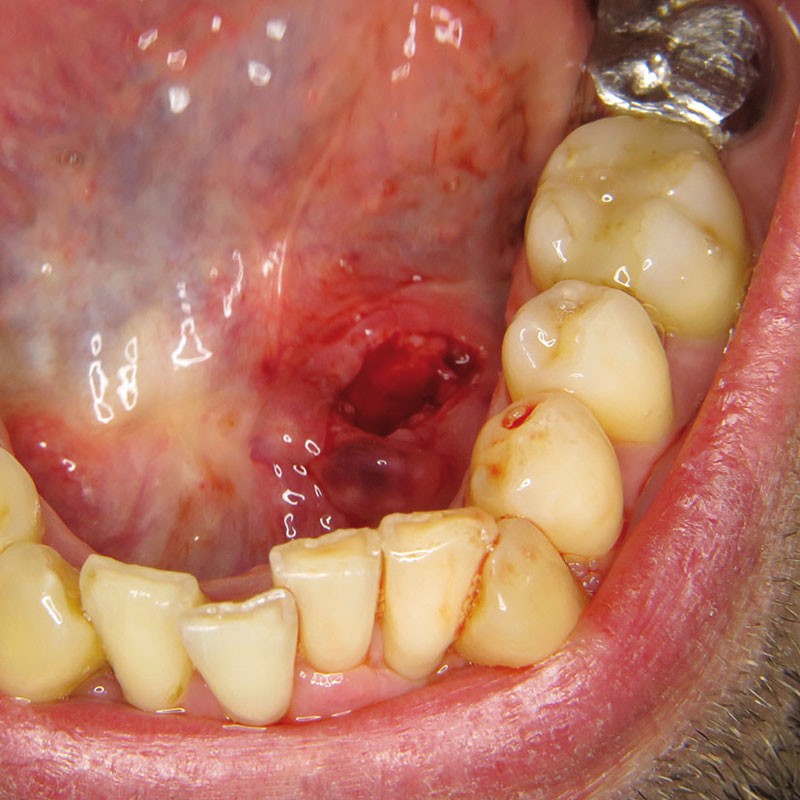

La prise en charge est chirurgicale sous anesthésie locale. Une incision du toit du nodule est réalisée (fig. 4 et 5).

La lithiase est libérée du canal aux ciseaux de Metzenbaum, ce qui permet son énucléation en un seul fragment de plus de 2 cm de grand axe (fig. 6).

Le canal n’est pas suturé, une suture du plan le plus superficiel est réalisée au Vicryl rapide 4/0.